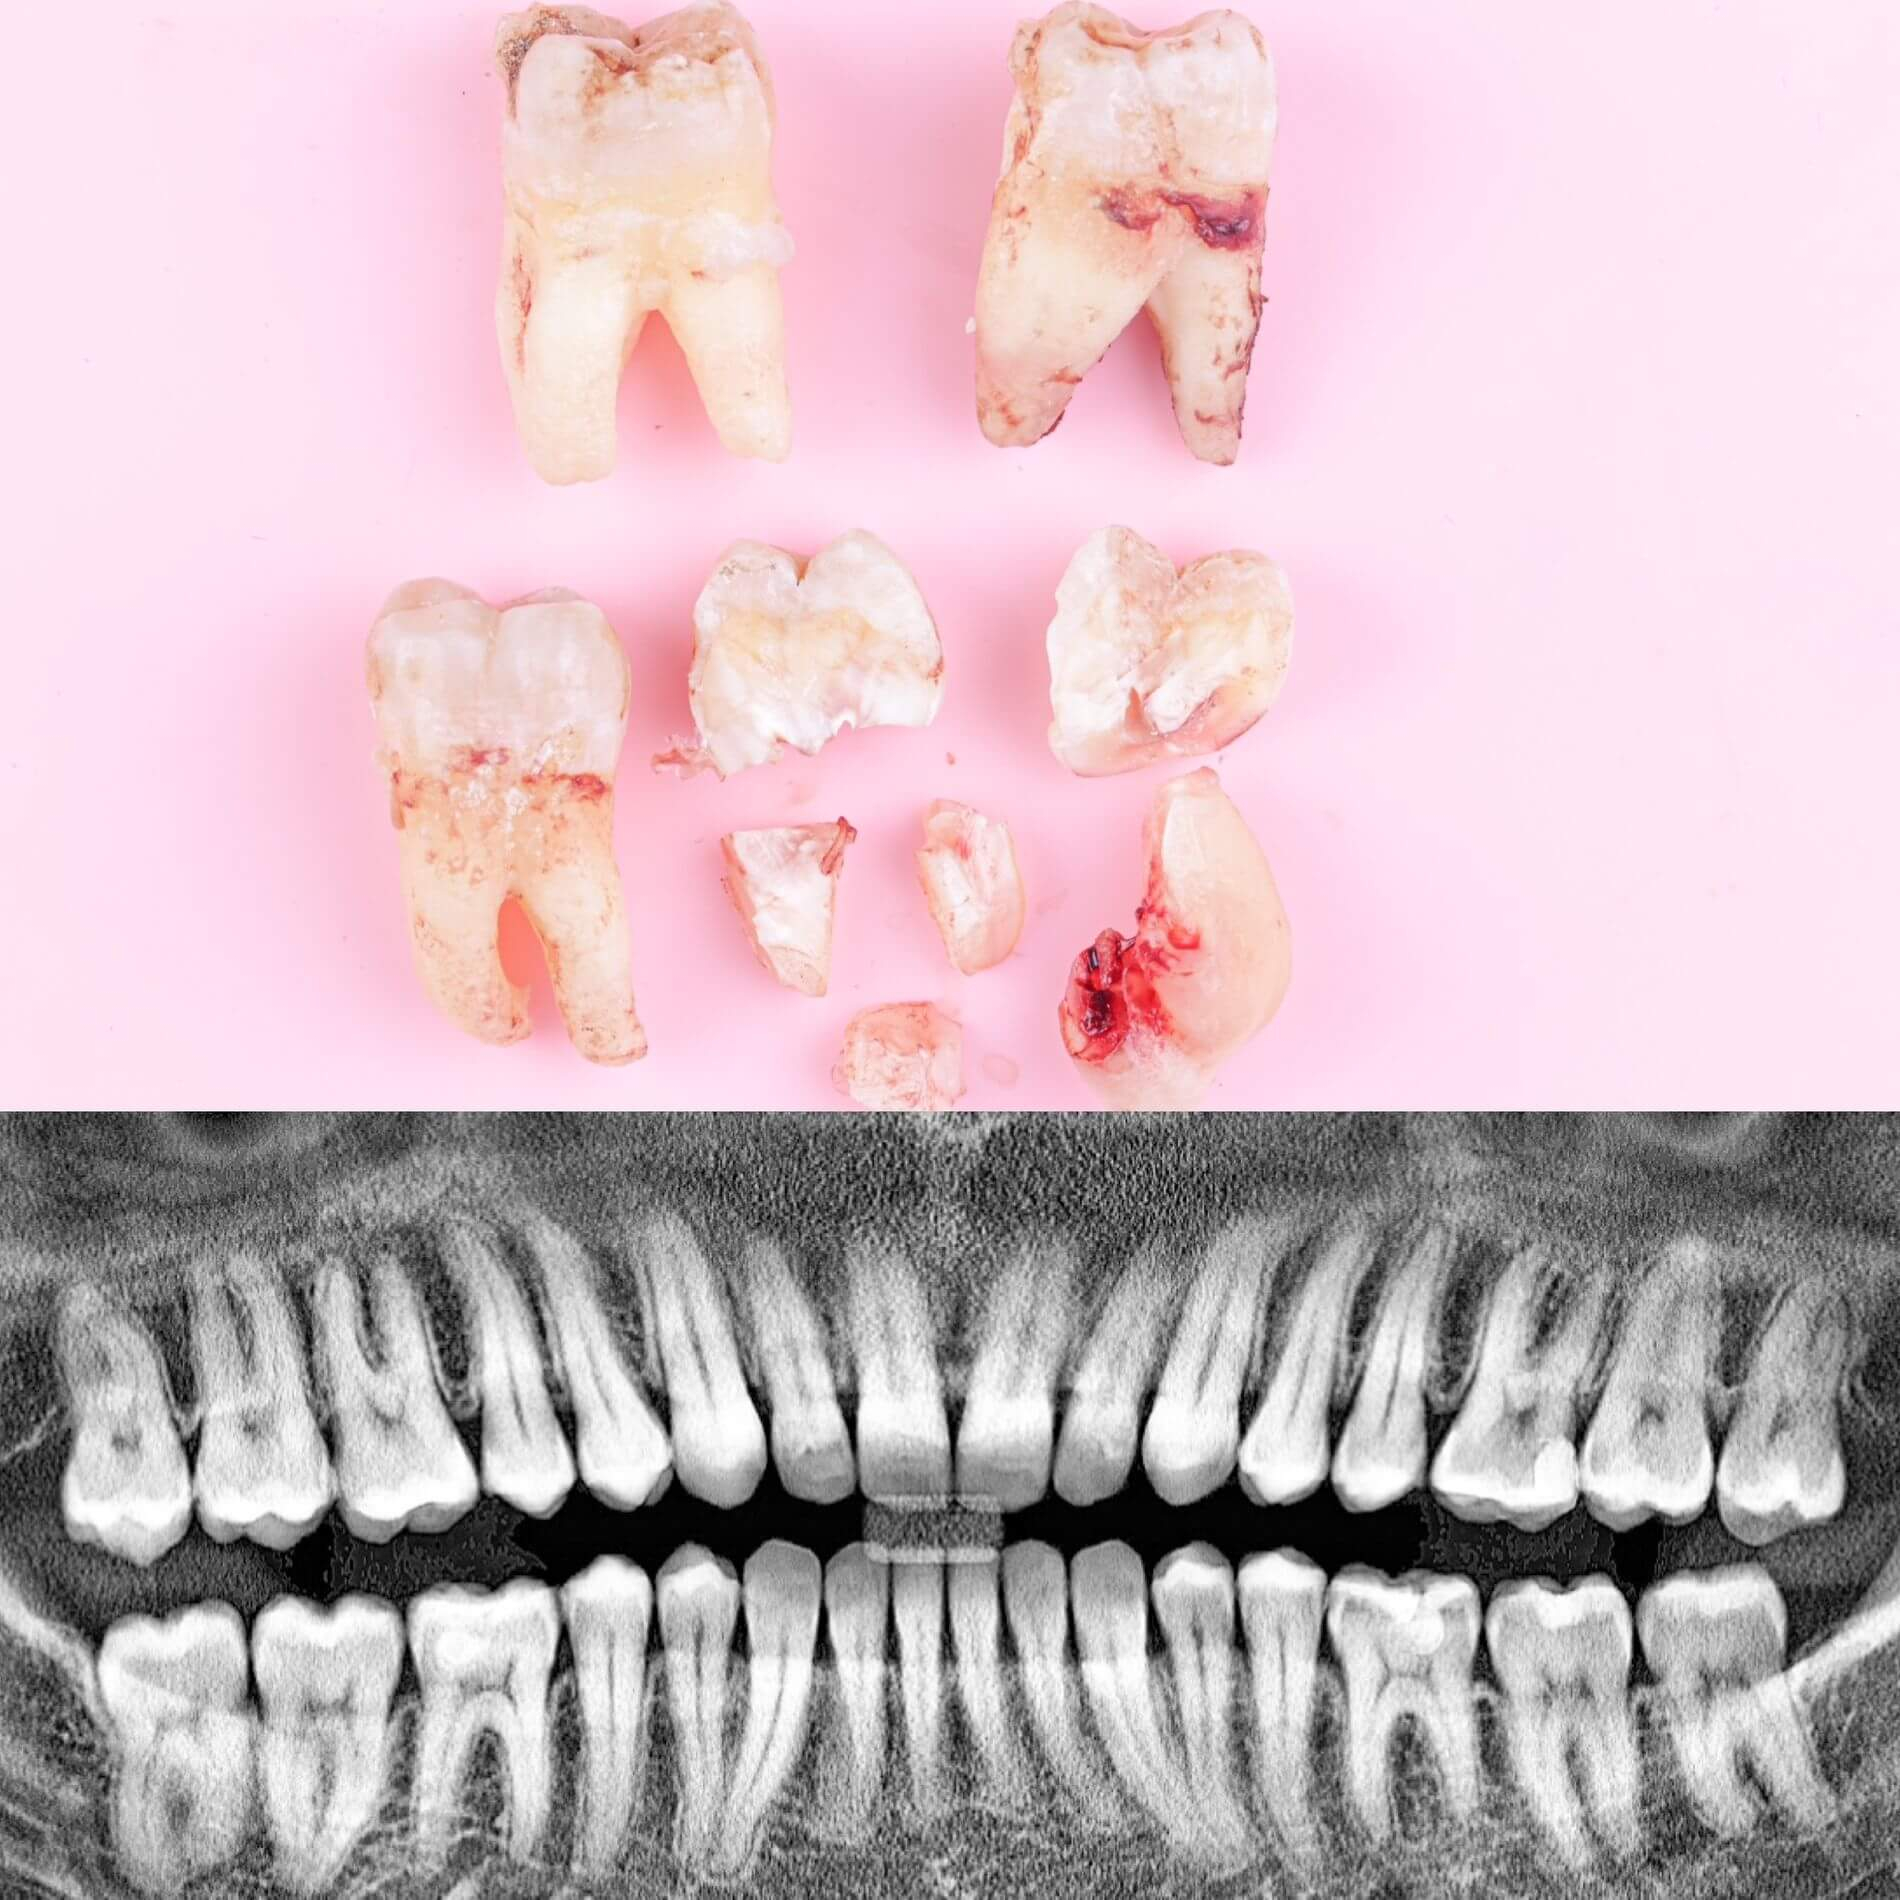

Галерея